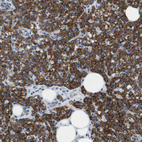

Immunohistochemistry analysis in human parathyroid gland and lymph node tissues using HPA015085 antibody. Corresponding MARC2 RNA-seq data are presented for the same tissues.